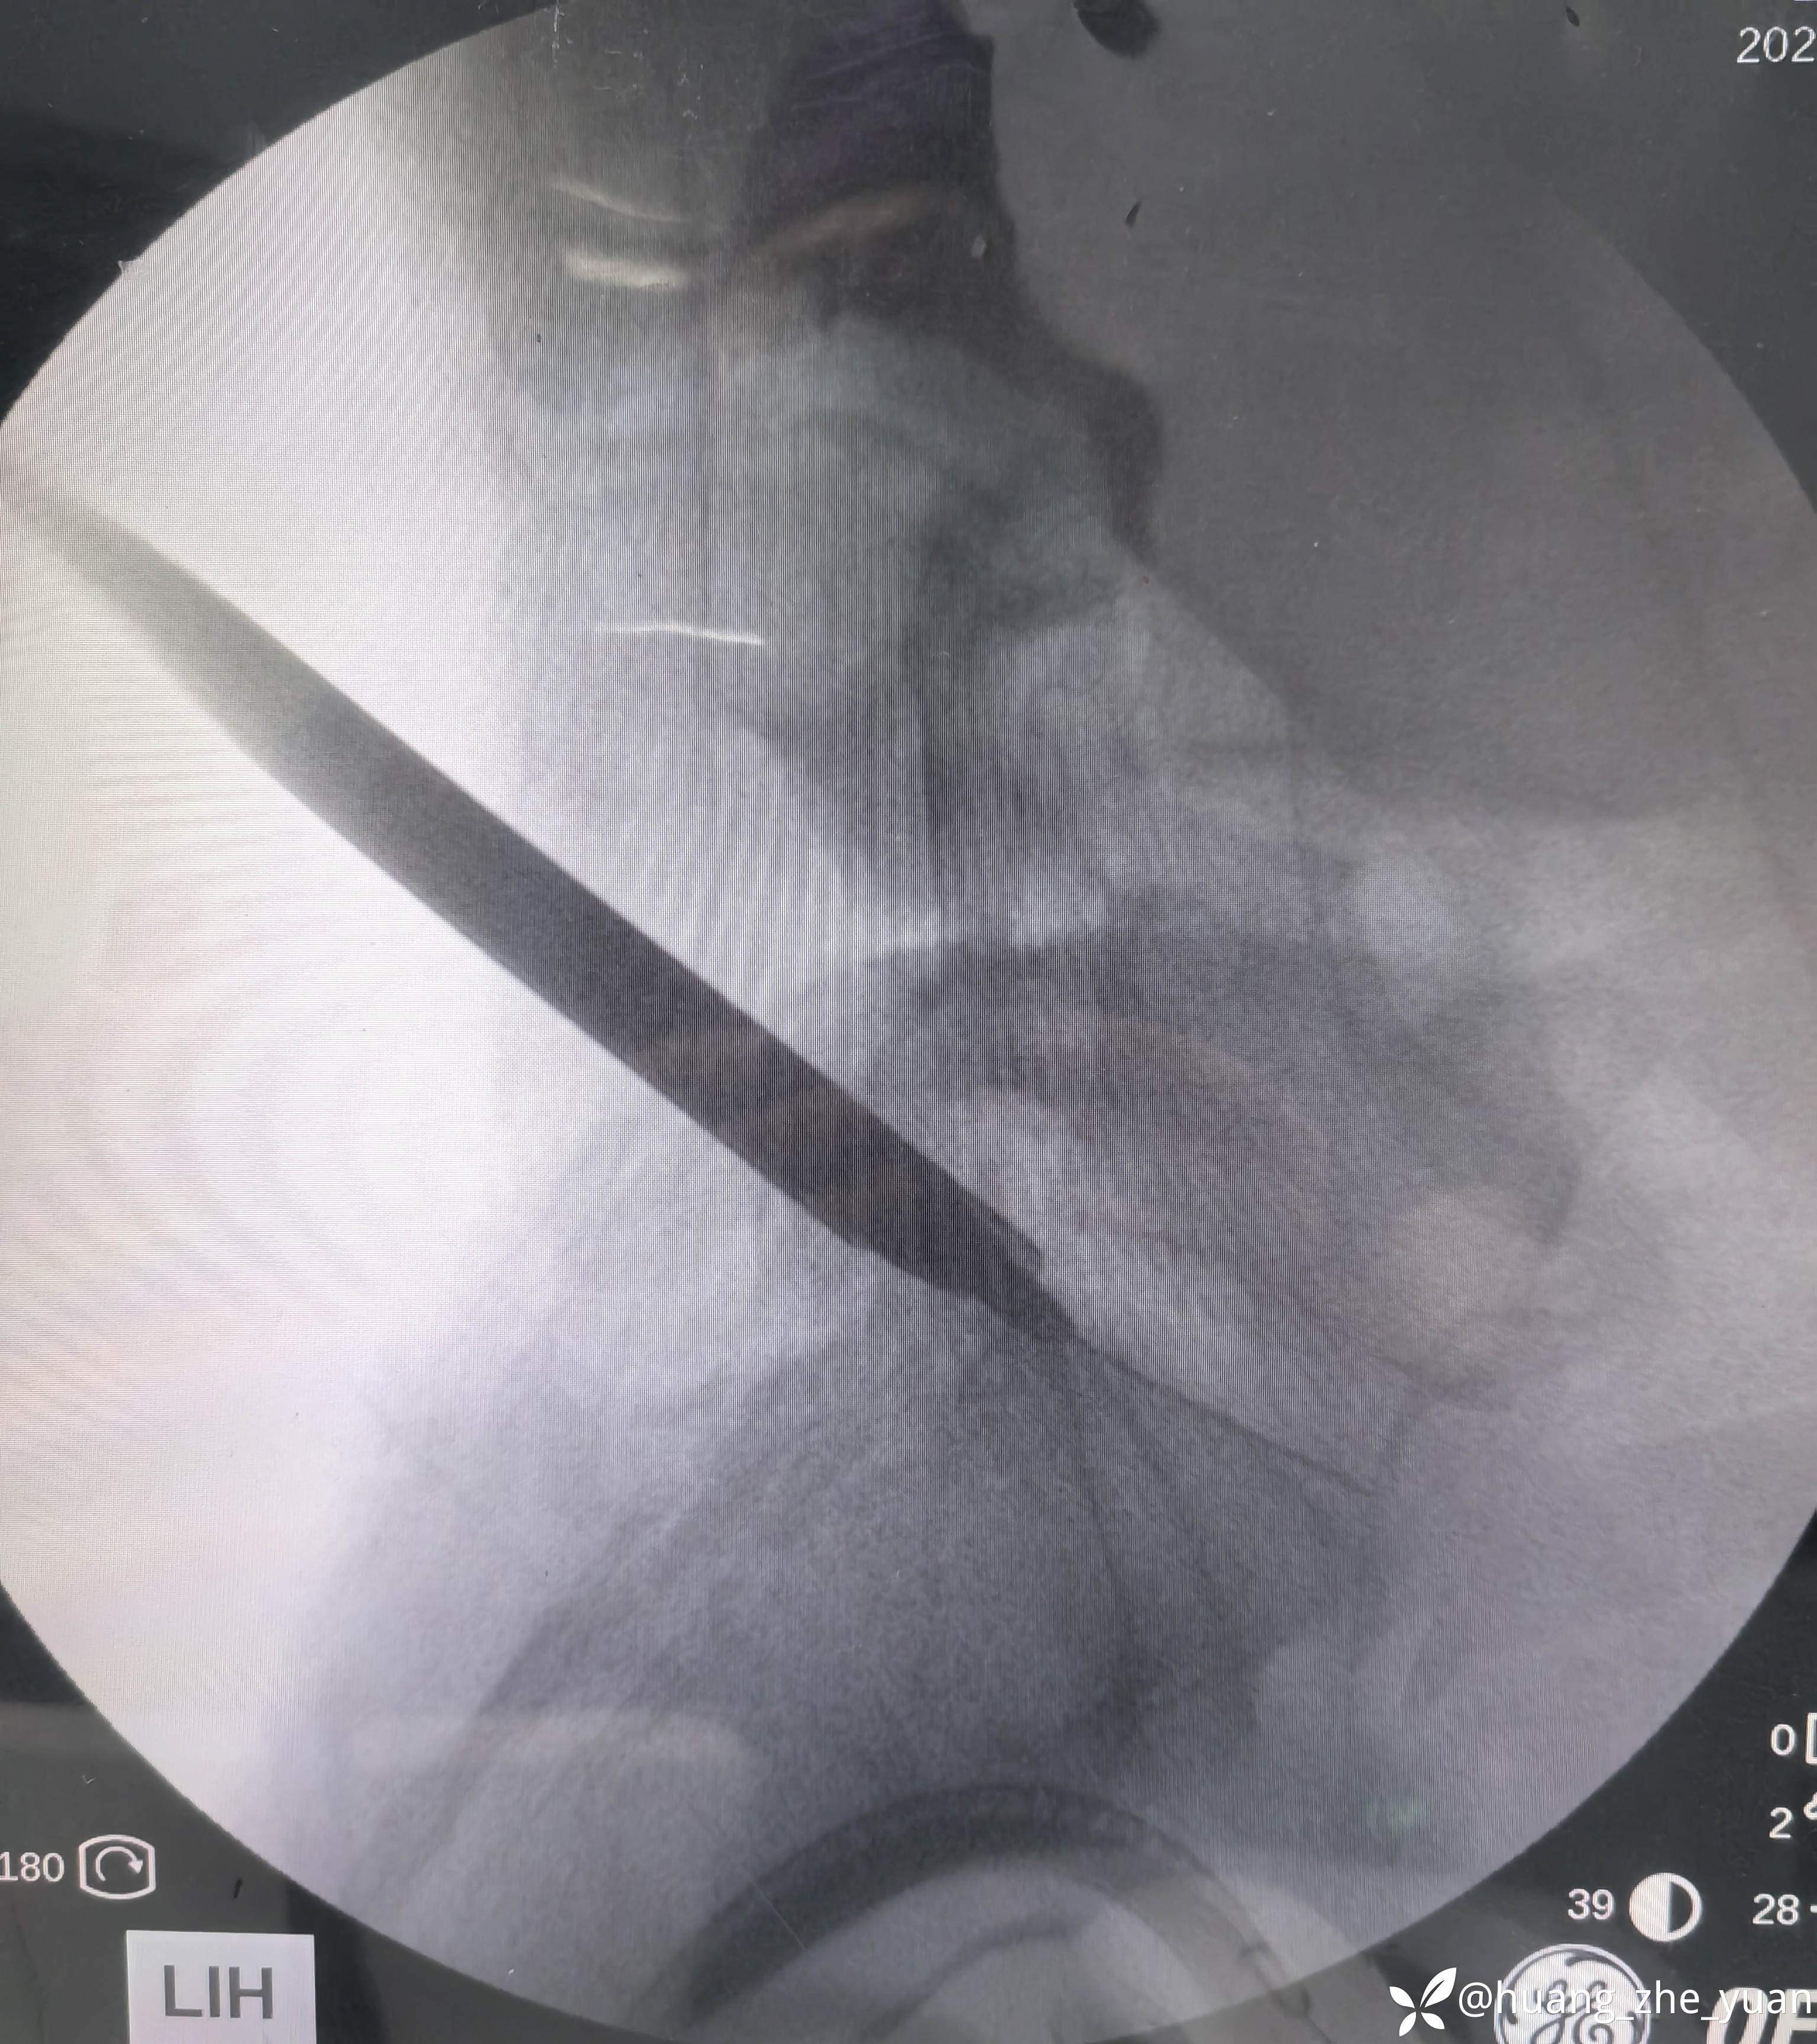

局麻单切口做两节。

椎间孔少量成形。椎间盘做微创消融。